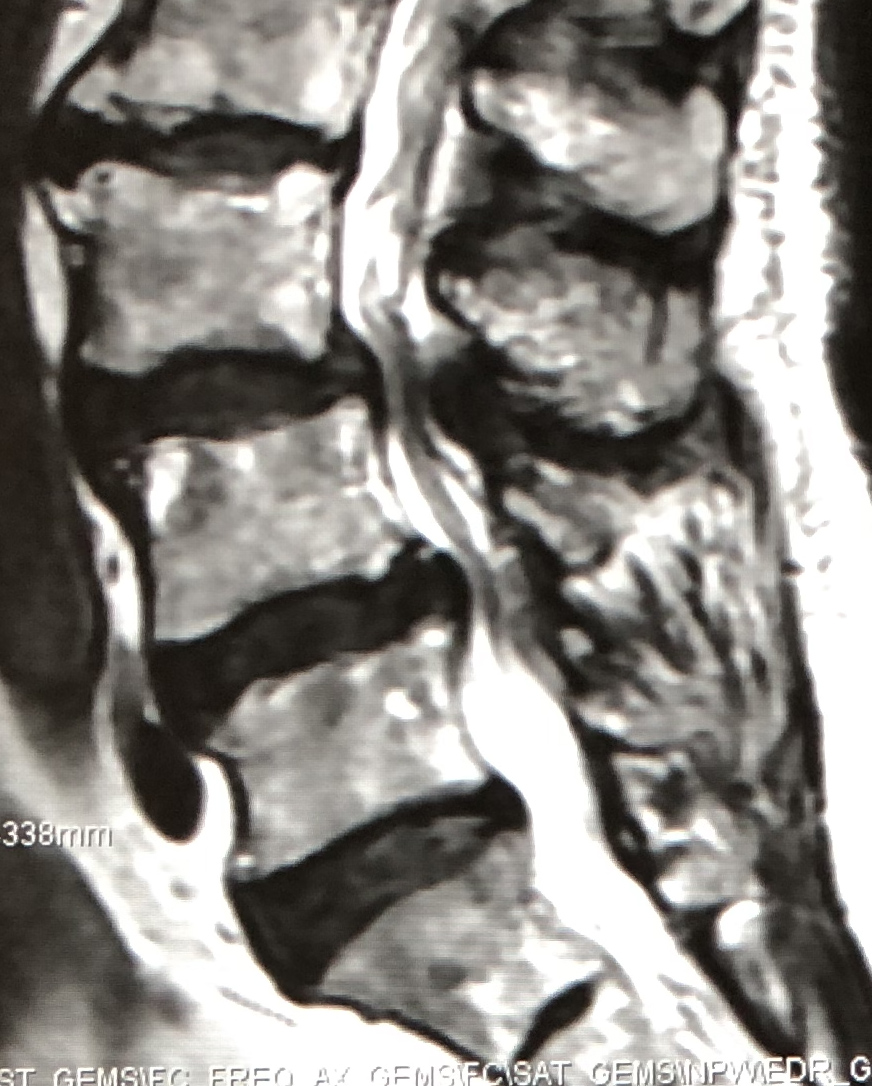

脊椎のすべりにより高度の脊柱管狭窄がある場合に、後方からすべりの矯正や神経の除圧が同時に行える手術です。

| 術前 | 術後 | |

| MRI |

|